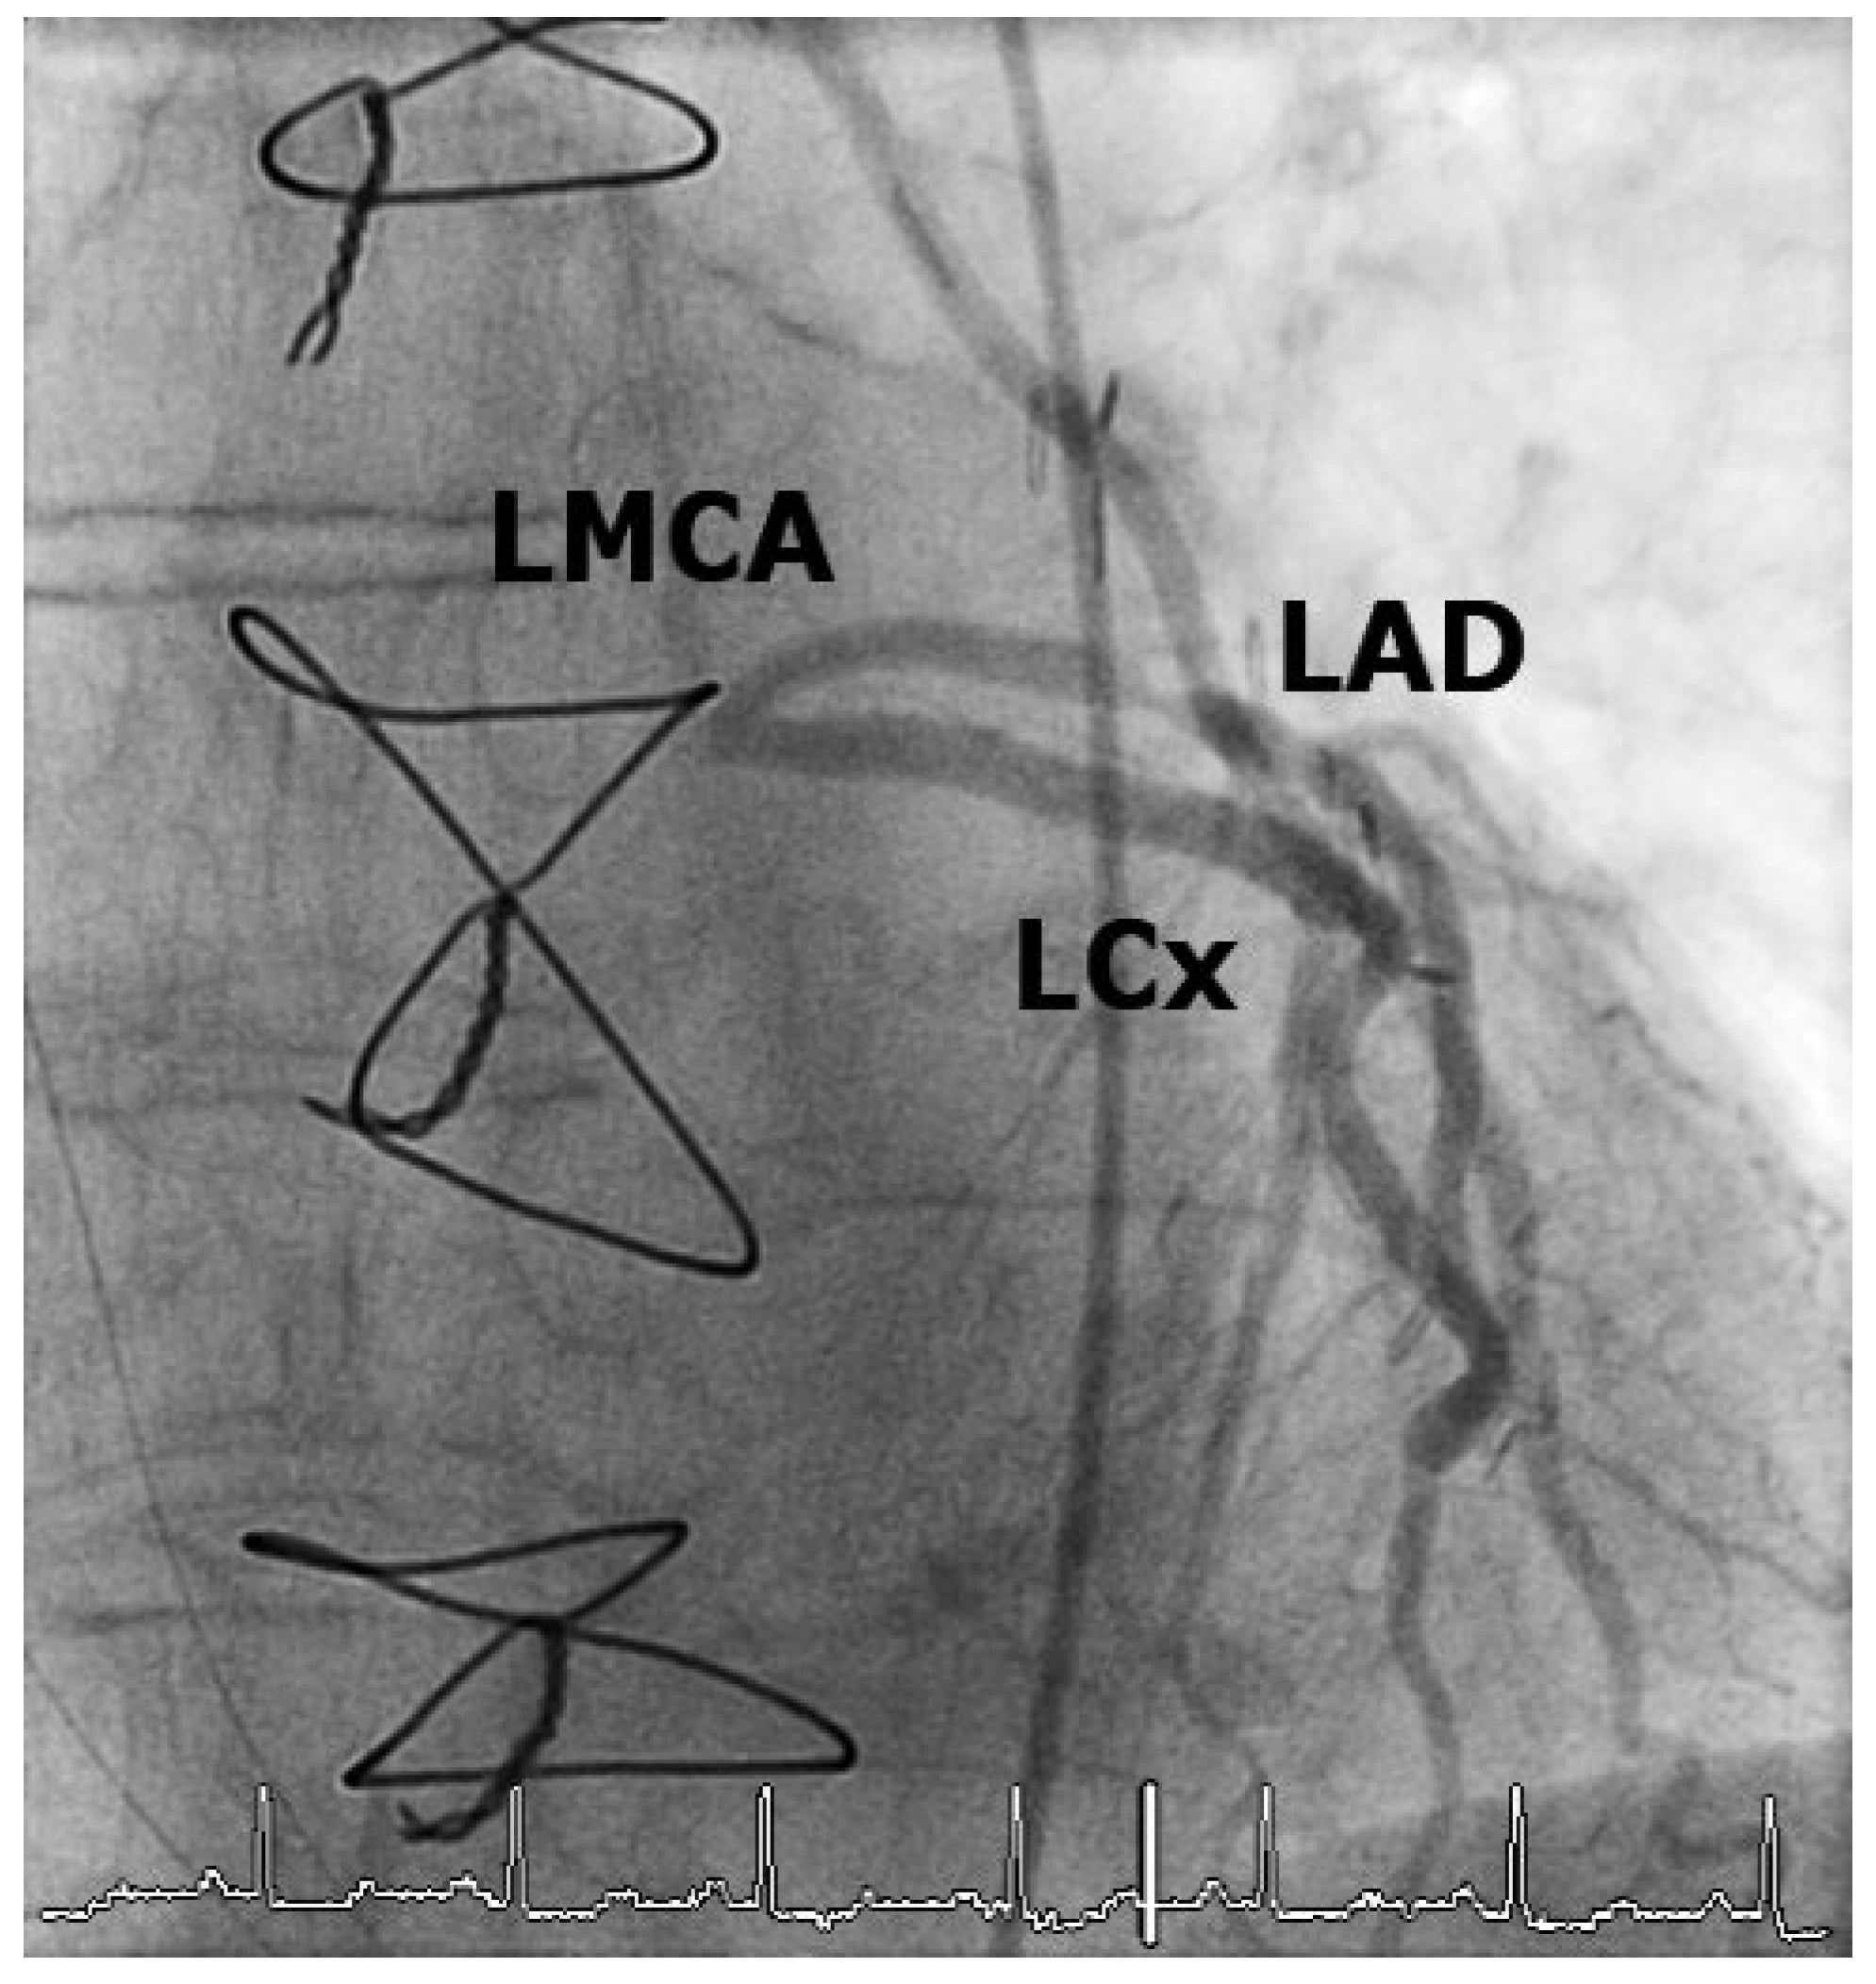

Case 1